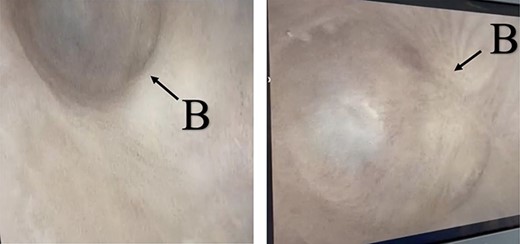

A 38-year-old male was referred to our tertiary hospital due to recurrent urethral stricture for further evaluation and management. His history revealed multiple failed attempts of DVIU, anastomotic urethroplasty and urethroplasty with pedicled fasciocutaneous flap in 2019. Nine months after his surgery, he had complete retention due to stricture recurrence and he underwent multiple dilatations and DVIU but his stricture keep recurring. He was referred to us for definitive management. He was on a suprapubic catheter. Initial workup included retrograde, antegrade cystoscopy and urethrogram. First, an antegrade cystoscope was introduced. The bladder neck, internal sphincter and verumontanum were identified. However, there was no external sphincter due to damage from the previous procedures. A pinpoint opening in the dorsal area of the urethra was seen about 1-cm distal to the verumontanum (Fig. 1, lumen A). Also, a blind-ended urethra in the ventral area was identified (Fig. 2, lumen B). It is most likely from the previous flap. Additionally, the retrograde urethrogram showed that the contrast was only going from the pinpoint hole in the dorsal side of the urethra Fig. 3. Retrograde cystoscopy also showed a blind-ended in the proximal bulbar urethra. We could not identify the small hole that we saw from the antegrade cystoscopy. After initial workup, he was counseled in the clinic for dorsal only buccal mucosal graft (BMG) urethroplasty for which he agreed.

(lumen B): A blind-ended urethra in the ventral area of the urethra as pointed in the arrow.